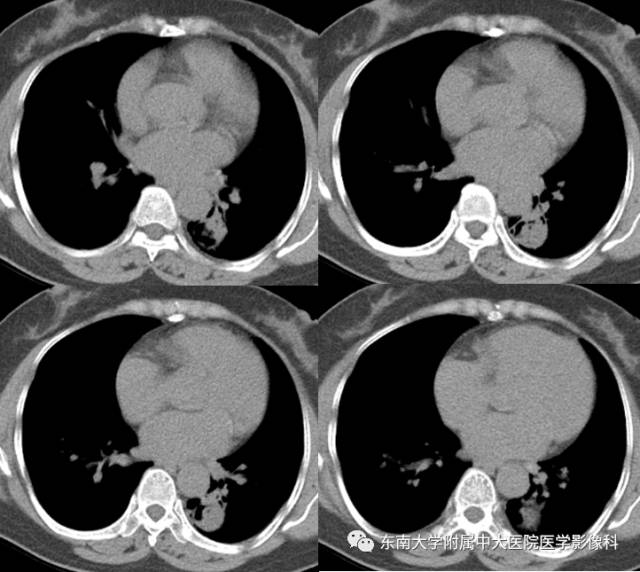

【病例】左下肺支气管囊肿伴肺曲霉菌感染

女,61岁,因“体检发现左肺占位1月余”入院。

CT